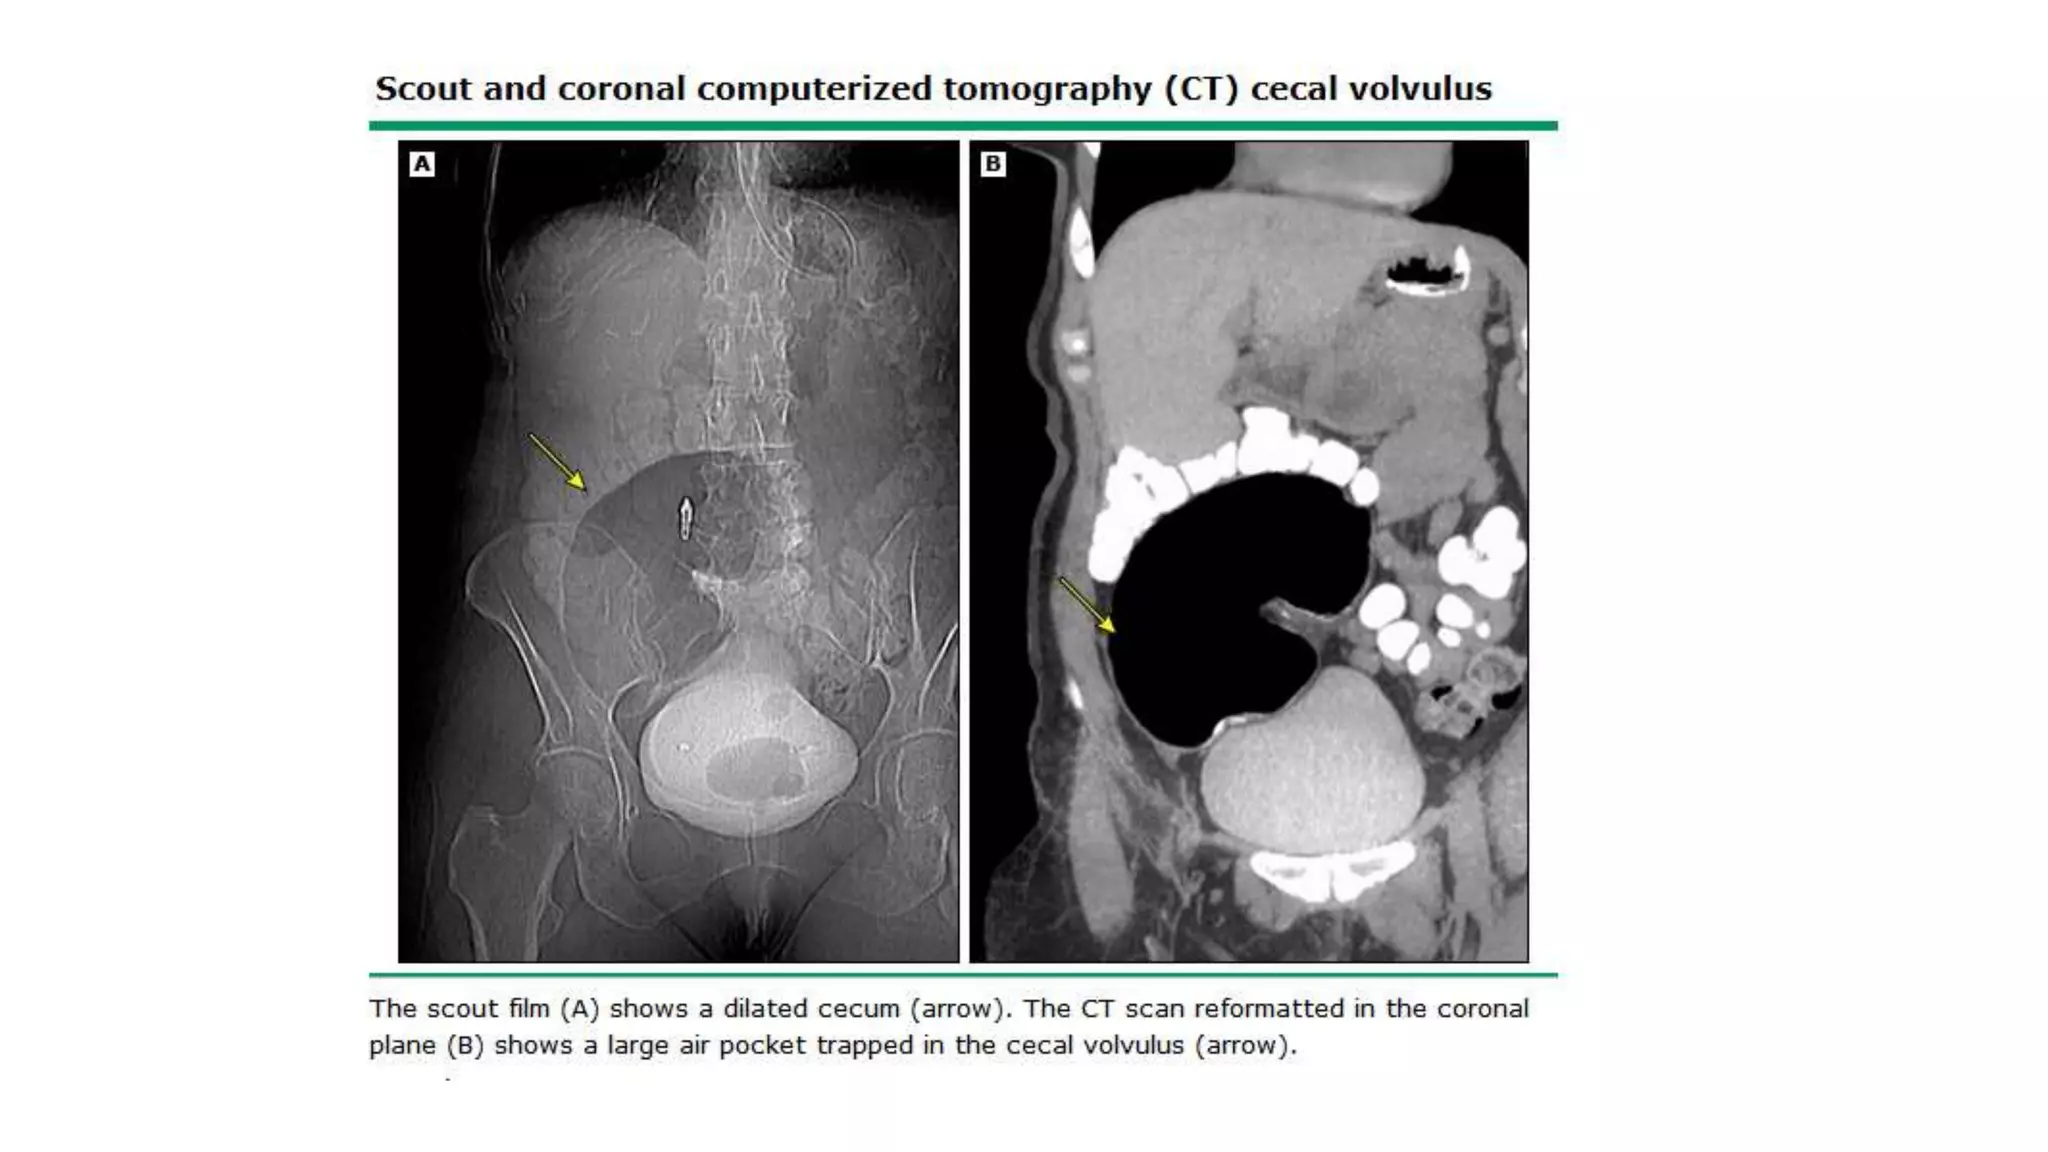

• CT scan — In patients with axial torsion of the cecum (type I or II), a

obstruction (a massively dilated cecum with associated small bowel

dilation) (image 5) or signs of colonic or small bowel ischemia (mural

thickening or mesenteric edema) [9]. In patients with a cecal bascule (type

III), CT scan shows the cecum folding upward, resulting in obstruction

without the axial twist of the mesentery (image 6).